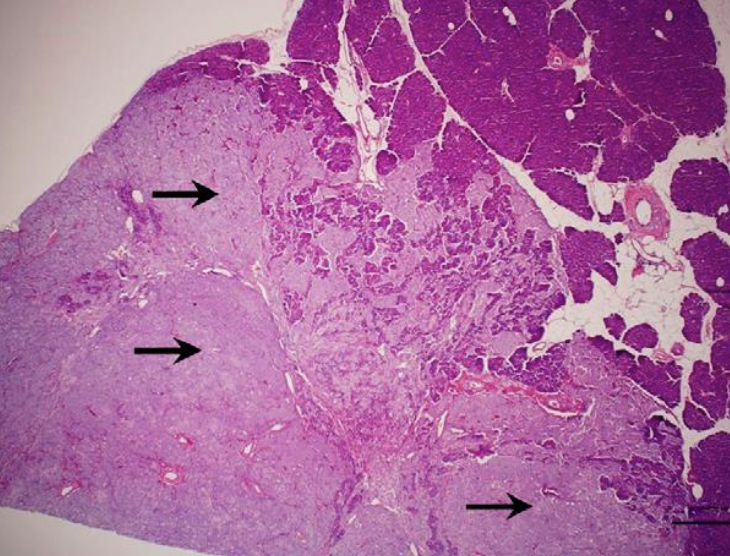

what is the biologic behavior of insulinomas in dogs?

-generally malignant tumors in dogs

-50% have metastatic lesions (regional LNs and liver, rarely the lungs)

histopathology

what should be performed during ex-lap for treatment of insulinomas?

-partial pancreatectomy

-resect suspected metastatic lesions when possible